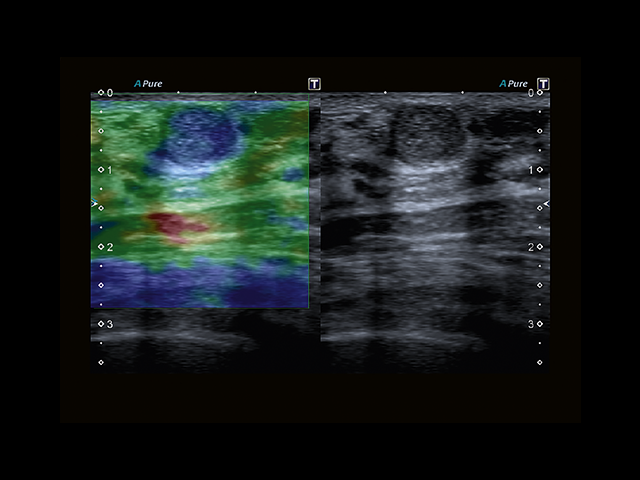

Обновленная версия легендарного УЗ-сканера. Стационарный аппарат экспертного класса Aplio 500 Toshiba NEW, визуализирует анатомические структуры в высоком разрешении. Модель позволяет выявить микрокальцификаты, новообразования, нарушения в работе сердца, сосудов и мышц. Присутствует функция виртуальной эндоскопии, 4D-сканирования, эластометрии тканей, УЗИ с контрастированием. За повышение качества изображения отвечают технологии ApliPure и Superb Microvascular Imaging. Первая задействует возможности пространственного и частотного кодирования, формирует цельный визуальный ряд с сохранением клинических маркеров. Вторая улучшает отображение микрососудистого русла, используя доплеровский эффект. Модель оснащена 21-дюймовым монитором, имеет 4 активных порта. Возможно подключение педиатрических, интраоперационных, лапароскопических и чреспищеводных датчиков.

• D-THI.Режим дифференцированной тканевой гармоники, повышающий качество визуализации глубоко расположенных тканей. Получаемое изображение отличается высокой четкостью, не содержит дефектов в виде «заснеженных» и размытых участков.